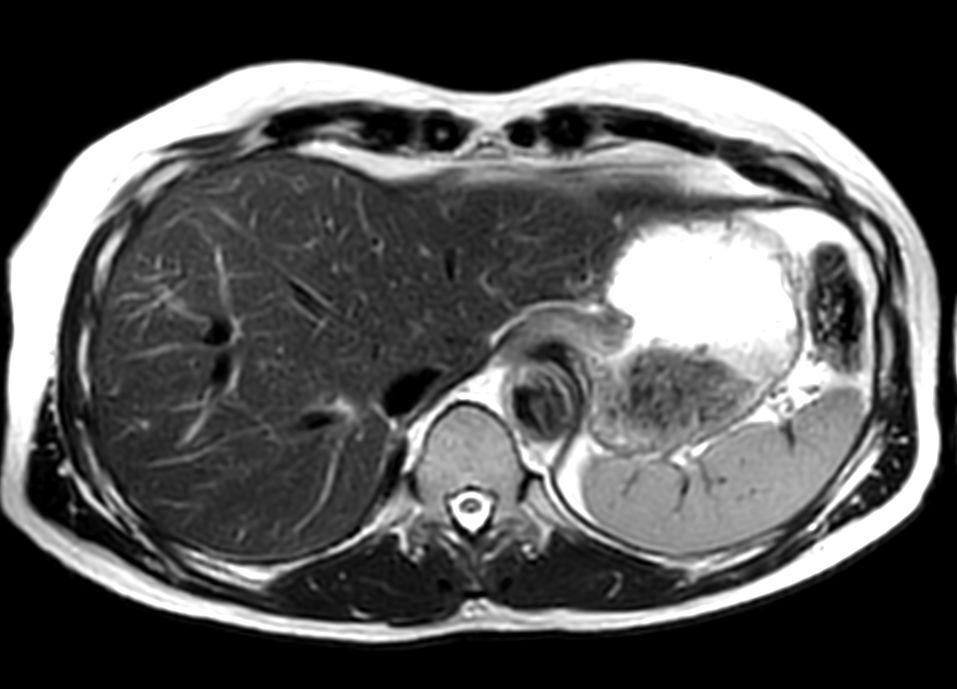

Coronal T1w FFE mDIXON (2 stations)Dual coil - Compressed SENSE